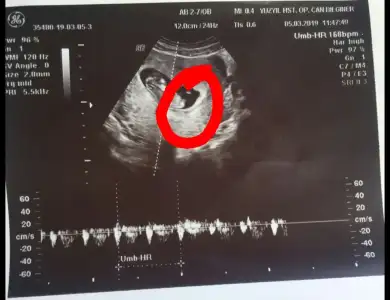

tatlım yazılanları okuyorum çıkıyorum kafam darma duman hayırlı haberler alırsın inşallah bu ay

canımcım gözün aydın olsun Rabbim sağ salim kucağına almayı nasip etsin oğlunu hayırlı salih evlat olsun

canım Rabbim sağlıklı sıhhatli evlat eylesin kızını doktor netse kızdır nubuda kıza benziyor zaten

Deneme yapan arkadaşlara diyorum tek ilişkiyle hamile kalmaya çalışın benim pik ve eşitken ilişki oldu ama muhtemelen pikken yaptığım ilişki tuttu geç çatladığı içinde kız tutundu bu düşüncedeyim takvimlerde bakmayın 20-25 tane takvim bulup not aldım 3-4 tanesi kız gerisi hep erkek çıkıyordu onlara aldanmak mantıklı değil bu arada rüyalarda herkezde aynı yorumlanmayabilir bende silah bıçak çok gördüm ama netice kızım oluyor önce sağlık demeyi unutmayın ben yeterince sağlıklı olsun dediğimi sonrada erkek evlat olsun diye dua ettiğimi sanıyodum ama erkek evlat olsun diye daha çok yakındım herhaldeki kızımın sağlığıyla sınanıyorum inşallah buda geçecek herşeyden önce sağlık sonra Rabbimin izniyle erkekleriniz olur inşallah